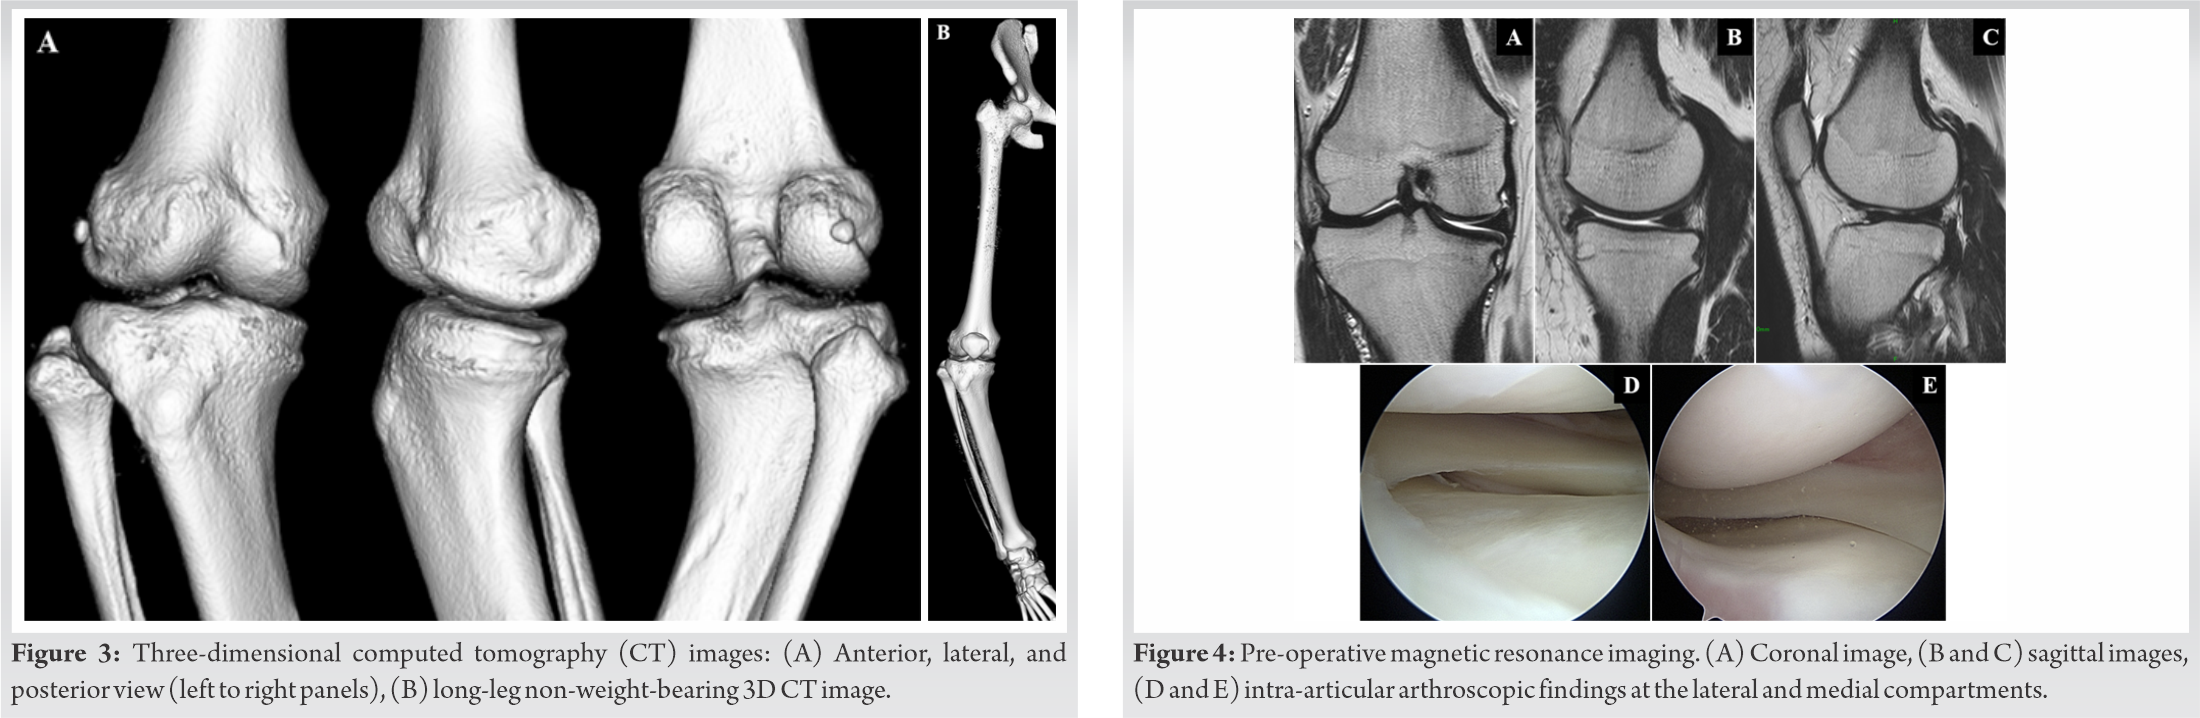

The range of motion (ROM) was 0° in extension and 135° in flexion. The subscales of pre-operative knee injury and osteoarthritis outcome score (KOOS) [7] (symptoms; pain; daily activities; sports and recreational function; and quality of life) were 89.29, 80.56, 82.35, 45, and 75, respectively. Bilateral anteroposterior long-leg weight-bearing radiograph (Fig. 1A-C) showed that the medial proximal tibial angle (MPTA), femorotibial angle (FTA), and the mechanical lateral distal femoral angle (mLDFA) in the right/left legs were 70°/89°, 204°/171°, and 94°/93°, respectively (Fig. 2A-C).The weight-bearing line ratio (WBLR) and non-weight bearing line ratio WBLR (non-WBLR) in the right/left legs were found to be −62%/54%, and −19%/42%, respectively. WBLR is defined as the horizontal distance from the medial edge of the tibial plateau to the WBL divided by the width of the tibial plateau (Fig. 2D). Detailed deformities were examined by using three-dimensional (3D) computed tomography (CT) images (Fig. 3A and B). Magnetic resonance imaging showed no abnormalities in the intra-articular anatomical structures, and the epiphyseal line was almost closed (Fig. 4A-C).

The surgery was performed as described in the previous studies [8,9,10]. At first, an arthroscopy was performed and no abnormal intra-articular abnormalities were detected (Fig. 4D, and E). The correction angle was set at 19° so that the post-operative non-WBLR would pass where the contralateral side passes. Lateral hemi-closed-wedge and medial hemi-opened-wedge osteotomy were performed, and then, the biplanar V-shaped osteotomy was completed (Fig. 5A-C). Next, the corrected tibia was fixed using a locking compression plate (Tris- Hybrid Lateral 2 HTO Plate system; Olympus Terumo Biomaterials Corp., Tokyo, Japan) (Fig. 5D). Then, the bone stock resected from the lateral tibia was implanted in the medial opening space (Fig. 5E).